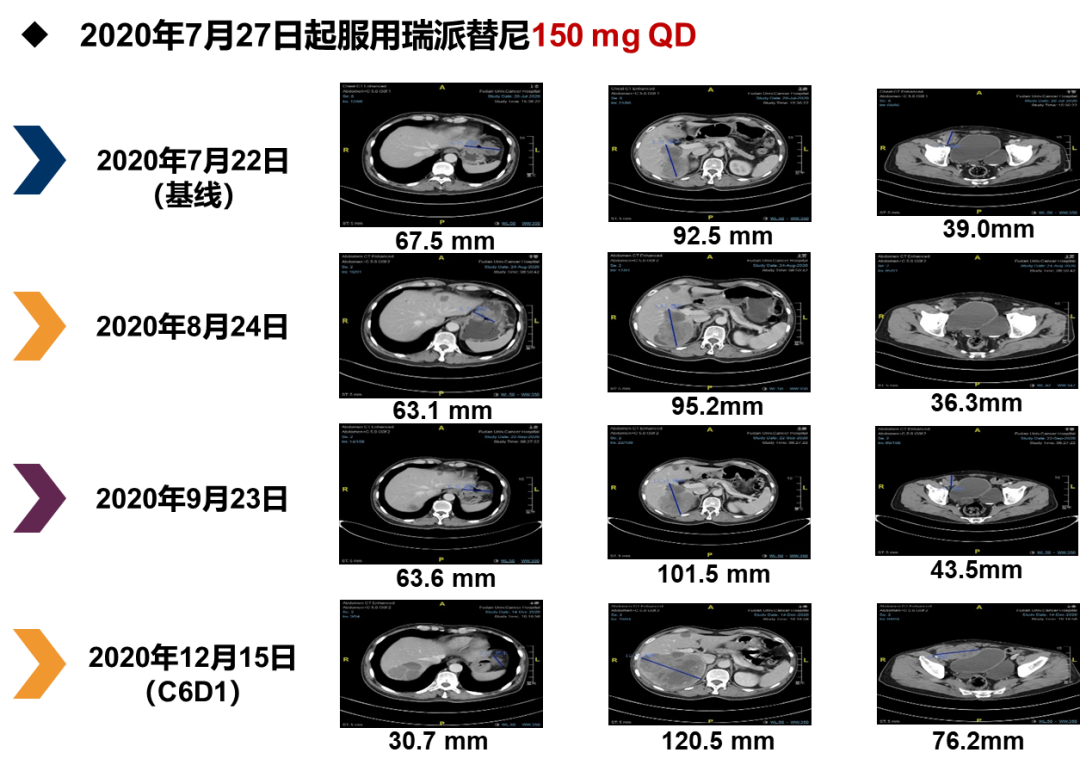

四线治疗(瑞派替尼150 mg QD,2020年7月至2020年12月)93a帝国网站管理系统

2020年7月27日,患者开始每日口服瑞派替尼150 mg治疗并定期复查,随访管理。93a帝国网站管理系统

2020年7月22日至2020年9月23日,肿瘤评估为SD。2020年12月15日CT评估为PD,PFS为4.8个月。在此期间患者出现的不良反应主要为贫血、乳酸脱氢酶增高、碱性磷酸酶增高、低蛋白血症和胆红素增高,均为1级,安全性良好。93a帝国网站管理系统

图片